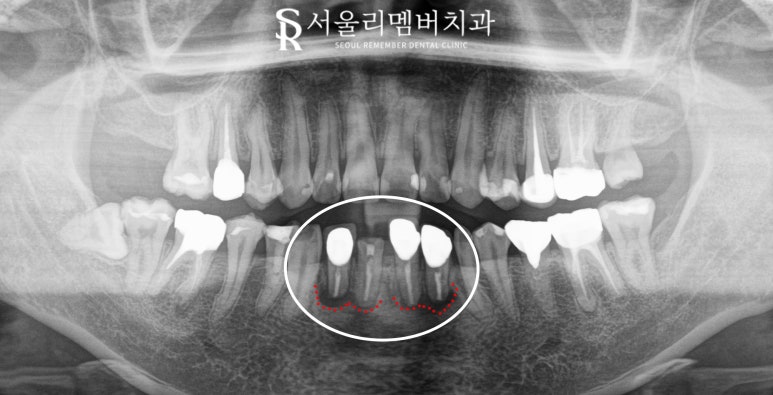

지금 보여드리는 사진은

방사선 사진의 종류 중에서

*파노라마(panorama)인데요,

구강 내 전체 치아는 물론이고

치조골의 높이와

턱관절, 상악동, 하치조 신경 같은

해부학적 구조도 살펴볼 수 있습니다.

이 케이스는 파노라마를 찍어보니

부러진 하악 전치가 눈에 띄는데

여기서 조금 더 주의 깊게 살펴봐야 될 것은

바로 뿌리 끝 염증입니다.

아마 과거에 신경치료를 하고

크라운을 씌워두셨던 것 같은데

시간이 지나면서 보철과 지대치 내부에 생긴

미세한 틈으로 세균이 들어가면서

치근단 끝에 염증이 생긴 것 같습니다.

물론 환자는 이미 신경치료가 다 되어있어서

통증을 느끼지는 못하셨겠지만

이렇게 근단 농양이 크게 존재한다면

발치를 하셔야 될 확률이 매우 높습니다.

그렇지 않으면 염증이 점점 커지면서

주변 잇몸뼈를 녹여버리고

주변 인접치에도 안 좋은 영향을 줄 수 있습니다.

봉천동 치과 에서 보기에

부러진 치아를 포함하여

뿌리끝 염증이 있는

총 4개의 아래 앞니를

발치하는 것이 좋겠습니다.